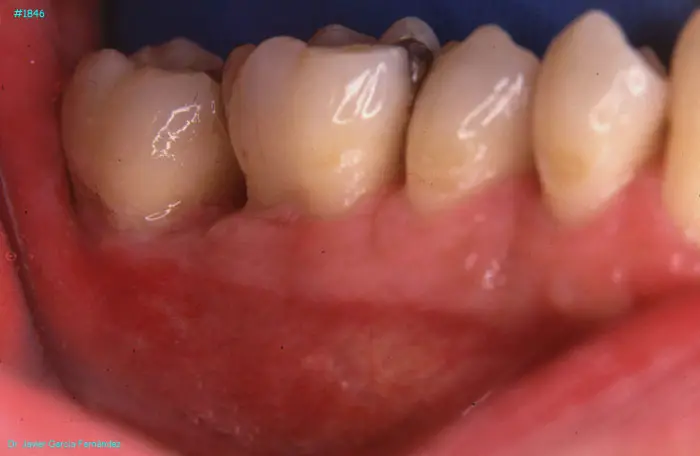

image 112